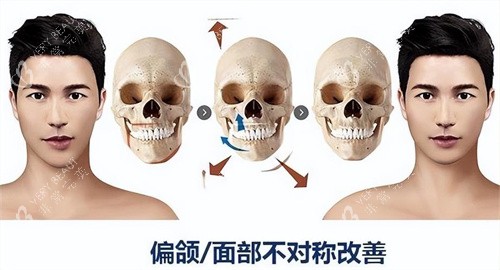

后来才知道,正颌手术分两种:一种是单纯牙性“地包天”,戴牙套就能矫正;另一种是骨性“地包天”,下巴骨头比上颌突出,必须动骨头。而我,属于后者。

“我们用3D截骨技术,先模拟你的术后结果,再精细截骨。”手术前一天,医生拿着我的3D模型,边比划边说。我盯着那个“虚拟下巴”,心跳得像打鼓——这要是截歪了,我后半辈子怎么办?

精细定位:医生用3D扫描我的头骨,在电脑上模拟截骨路线,连0.1毫米的误差都要算清楚。

减少损伤:传统截骨靠医生经验,容易碰到神经;3D技术能避开血管和神经,术后肿胀轻一半。

结果可预:手术前就能看到术后侧脸,不像以前“盲做”,做完才发现“不是想要的”。